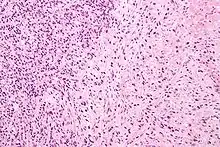

Gleason pattern 4 (left of image) and Gleason pattern 5 (right of image). H&E stain.

• Pattern 5 - The tissue does not have any or only a few recognizable glands. There are often just sheets of cells throughout the surrounding tissue. This corresponds to an anaplastic carcinoma.

Gleason 5

Neoplasms have no glandular differentiation (thus not resembling normal prostate tissue at all). It is composed of sheets (groups of cells almost planar in appearance (like the top of a box), solid cords (group of cells in a rope like fashion running through other tissue/cell patterns seen), or individual cells. You should not see round glands with lumenal spaces that can be seen in the other types that resemble more the normal prostate gland appearance.[4][7]